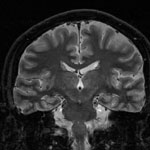

Inversion recovery 法による脳の冠状断像。

海馬の層構造が確認できる。